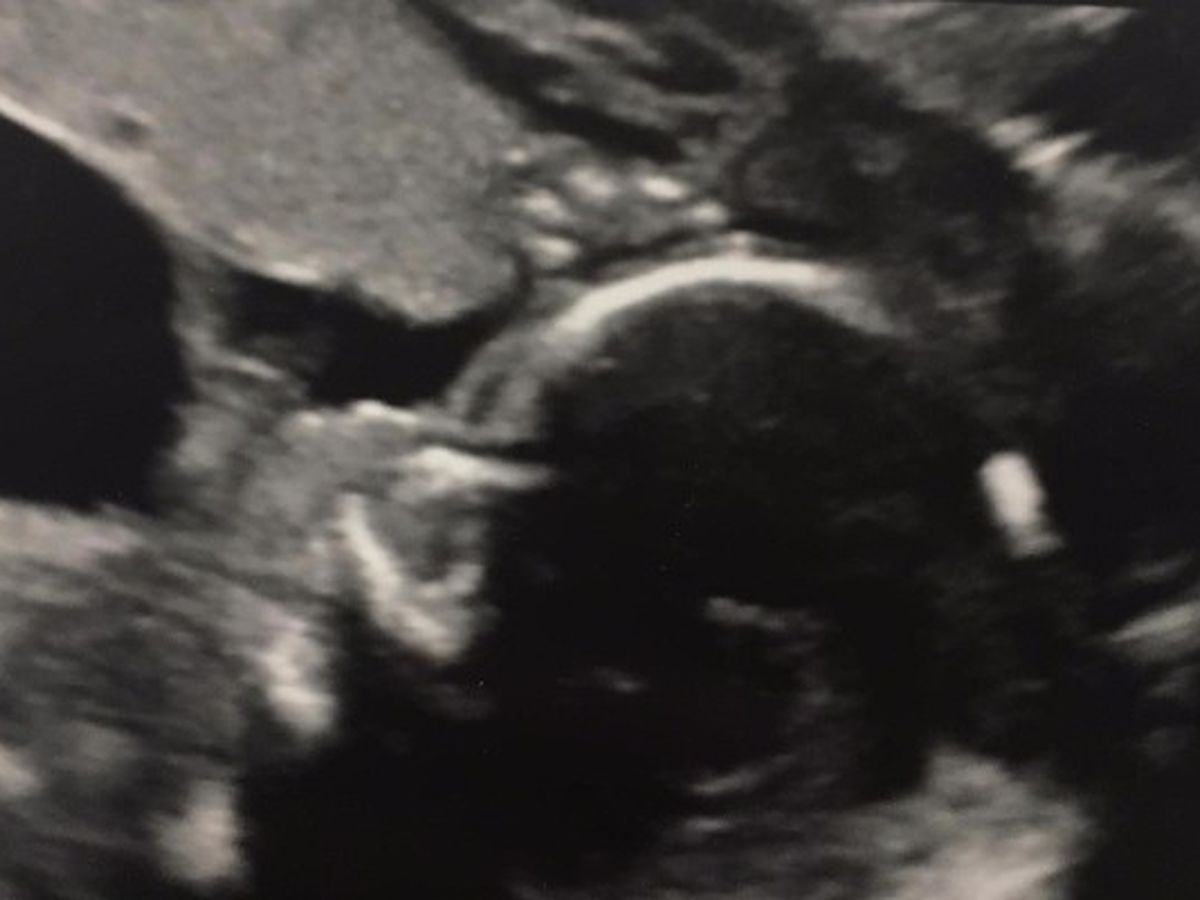

Our son Connor Isaac Houde was diagnosed with a rare disorder called prune belly syndrome. This is caused by a lower urinary tract blockage and keeps the baby from emptying his bladder. The bladder swells almost to the size of the mother's and causes pressure on the kidneys. Because of the pressure the kidneys have formed many cysts and he will have kidney problems at birth that may require dyalisis or transplants when he is old enough. Another issue with Connor is he has low amniotic fluid, this puts him at a higher risk of crushing his cord and will cause him to have underdeveloped lungs since he doesn't have as much room to move, expand and grow.